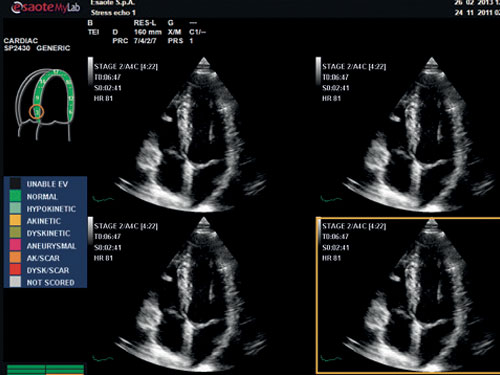

Stress echo: Kompletní balíček stress echa s flexibilními a přizpůsobitelnými protokoly pro získávání a kontrolu zobrazování, k dispozici také u LVO.